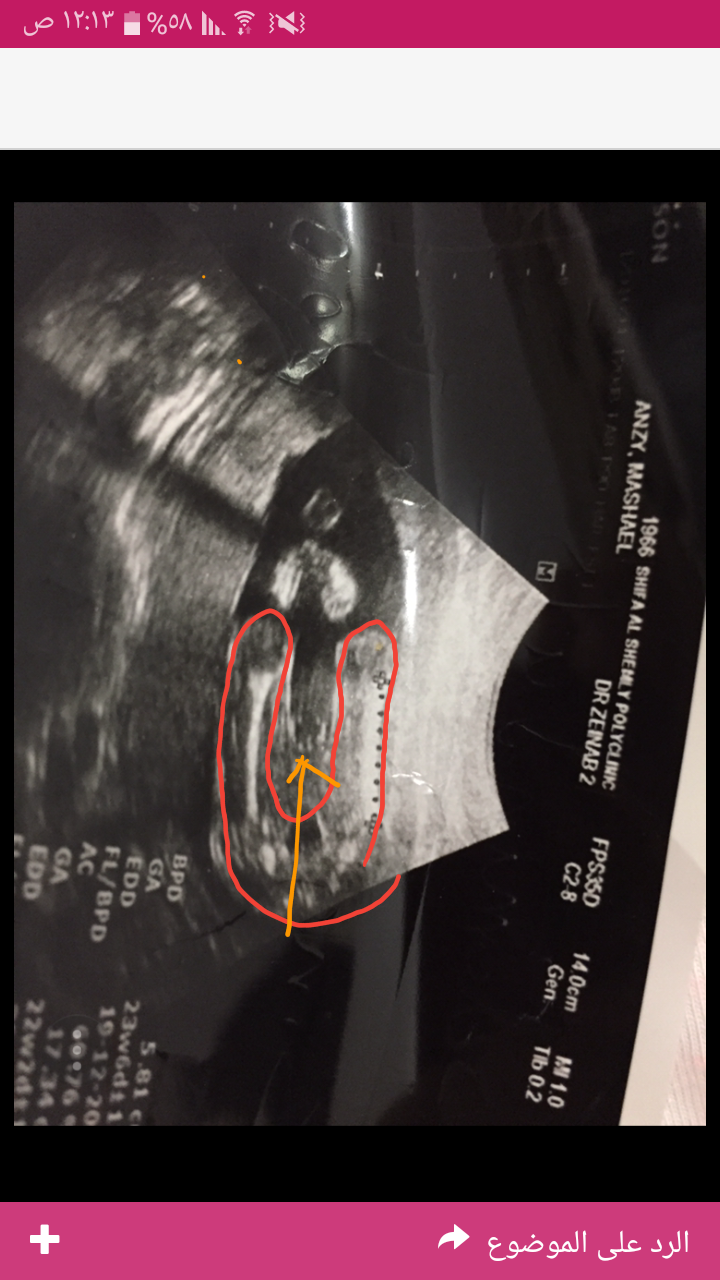

عزيزتي انا اعرف بالسونار بشكل ممتاز . وبعد مشيئة الله هذه بنت . التحديد الاحمر هذول عظمة الفخذ للجنين عل شكل U كانه نايم على ضهره وماسك رجوله بدينه الثنتين تخيلتي الشكل. السهم البرتقالي مشار اللى العضو الانثوي وهي خطين ابيض وهن الشفرات وخط بالمنتصف اسود . انشالله اكون وضحتلك الله يتمملم على خير.